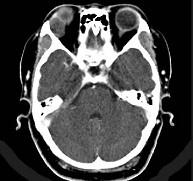

泪腺肿瘤(如图)使眼球 ( )A、向颞上方移位B、向鼻下方移位C、向上方移位D、向颞下方移位E、呈轴性前突

问题 泪腺肿瘤(如图)使眼球 ( )

选项 A、向颞上方移位 B、向鼻下方移位 C、向上方移位 D、向颞下方移位 E、呈轴性前突

答案 B